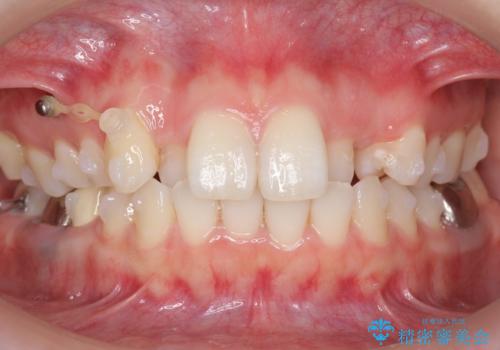

- 前歯のがたつきを主訴に来院。

左上の犬歯が歯肉退縮しており、そこを抜歯して矯正することにしました。

右上については、奥歯をインプラント矯正により後ろに動かして、引っ込んだ前歯を並べるスペースを確保しました。